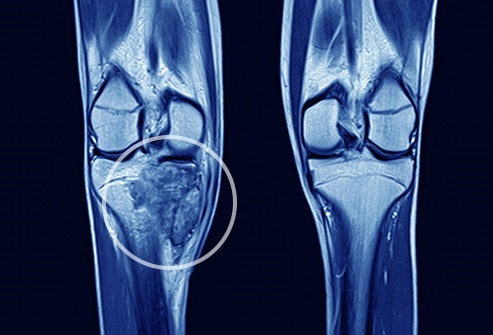

Primary bone cancers are also known as sarcomas. There are various types of sarcoma. The beginning of each tissue is found in a different bone tissue. The most common sarcomas are the Ewing’s sarcoma, Chondrosarcoma and Osteosarcoma.

In young people, Osteosarcoma is considered to be a very common type of bone cancer. usually, this bone cancer occurs between the ages of 10 and 25. More often, it will affect the men than the females. The beginning of Osteosarcoma is frequently seen in the ends of the bones. Here, the new bone tissue will be formed as a young person will grow. Usually, the long bones of the legs and arms will be affected.

Chondrosarcoma is also a type of tumor that will be formed in the cartilage. This is mainly found in the adults.

The most common symptom of this disease is the pain. However, there is a variation of symptoms depending on the size and location of cancer. Sometimes, tender or firm lumps can also be noticed through the skin. Sometimes it will interfere with the normal movements as well. The bones may be weakened or may be broken. Tumors that will occur in the joints can also cause tenderness and swelling in the bones.